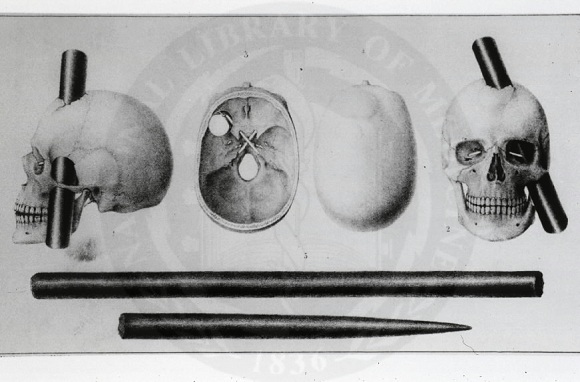

1948 senesinde Amerika’da nörobilim dünyasını yüz yıldan fazla etkisi altına alan talihsiz bir kaza gerçekleşti. O sıralarda Phineas Gage adlı 25 yaşında bir genç, demiryolu fabrikasında çalışıyordu. Fabrikadaki bir patlama sonucu, yaklaşık 1 metre uzunluğunda ve 3 santim çapında demir bir boru, Gage’in sol elmacık kemiğinden girip, kafatasının ön kısmında bir delik yarattı. Deliğin ön frontal kortekste oluşturduğu ağır hasara rağmen, Gage kaza sırası ve sonrasında; ne bilincini, ne de hafızasını kaybetmişti. Gage’in beyninin tüm fonksiyonları yerinde gözüküyordu, eskisi gibi konuşabiliyor ve yürüyebiliyordu. Eskisine göre yerinde olmayan tek özelliği, kendini kontrol etme yeteneğiydi. Gage tamamen yeni bir kişiliğe bürünmüştü. Onu eskiden tanıyanlar ona “No longer Gage” ismini takmışlardı ve Gage’in yeni halini irrasyonel ve karmaşık buluyorlardı. Tüm arzu ve duyguları tamamen dürtüsel şekilde işliyordu. Çalıştığı fabrikanın lojistiğine hala hakim ve fiziksel olarak eskisi gibi çalışabilecek durumda olan Gage, duygu ve dürtülerini kontrol etme yeteneğine sahip olmadığından, iş arkadaşlarıyla geçimsizlik sebebiyle işten çıkarıldı.

Beynimizde duygularımız oluşurken, merkezi sinir sisteminden gelen duyu sinyalleri; gördüklerimiz, duyduklarımız ve hafızamızda kaydettiklerimiz, kompleks bir filtreden geçer ve beynin ortasindaki limbik sisteme ulaşır. Limbik sistem, Gage’in zedelenen ön korteksiyle doğrudan bağlantılıdır Duygular ikinci filtreye burada alınır ve rasyonelleştirilir. Bazen öfkeden birilerine veya kendimize zarar verecek bir şeyi yapacakken kendimizi durdurabilmemiz, ön korteksin dürtülerimizi frenlemesi sayesindedir. Gage gibi beyinin ön korteksinde zedelenme meydana gelmesi veya demans gibi merkezi sinir sisteminin bazı kısımlarını yok eden hastalıklar sonucu ön korteksi eskisi gibi çalışamayan kişilerde, duygu ve dürtülerin kontrol edilmesi imkansızlaşır.